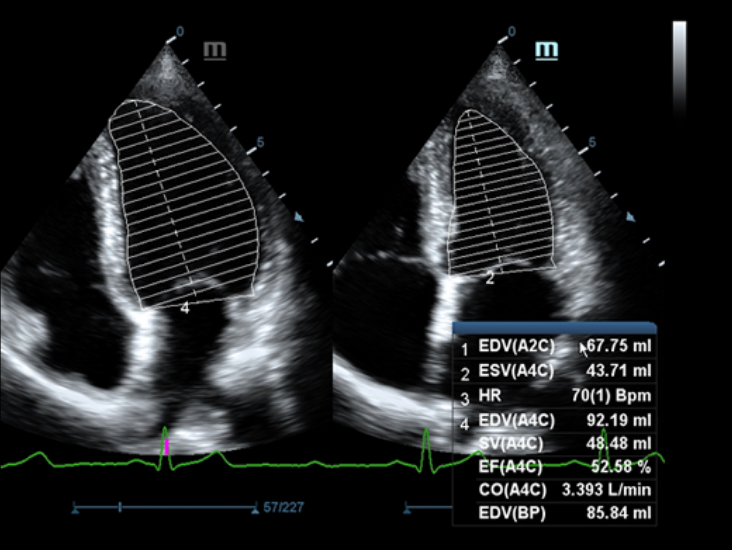

Специализированный уход благодаря ECHO

Многофункциональная система DC-60 Exp с X-Insight представляет собой комплексное решение, которое помогает управлять повседневной клинической практикой с легкостью и уверенностью.

Основываясь на глубоком понимании потребностей клиентов, компания Mindray разработала систему DC-60 Exp с X-Insight, чтобы обеспечить высокую производительность и точность визуализации вкупе с наглядностью, исключительной интеллектуальностью и огромным опытом.

Опыт работы и высокая производительность